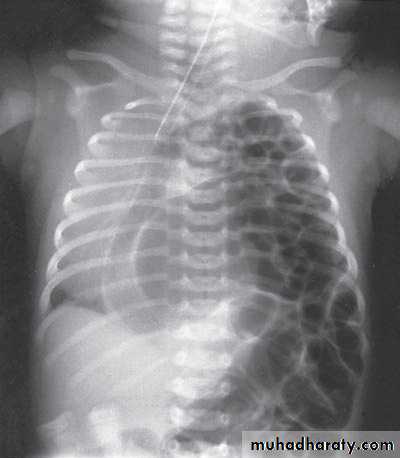

Scaphoid abdomen